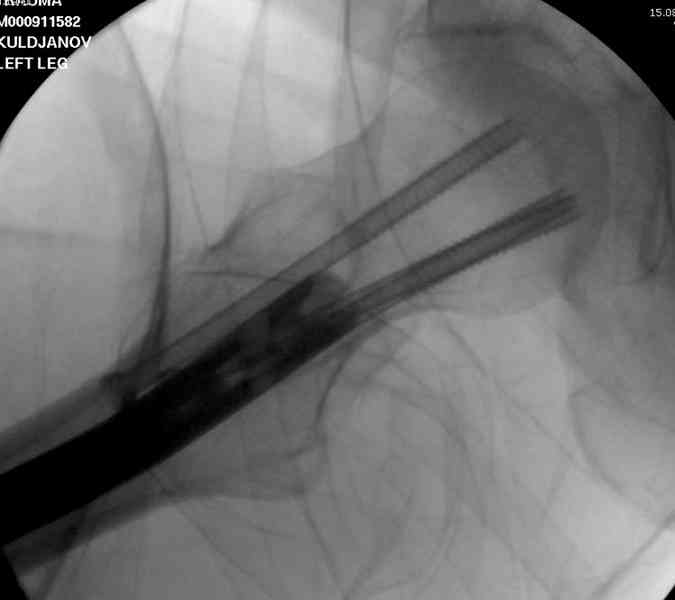

На второй день (7) обнаружен пропущенный перелом,

сделаны Компьютерная Томограмма

и проведены шурурпы через и спереди штифта без удаления.

Послеоперационные снимки